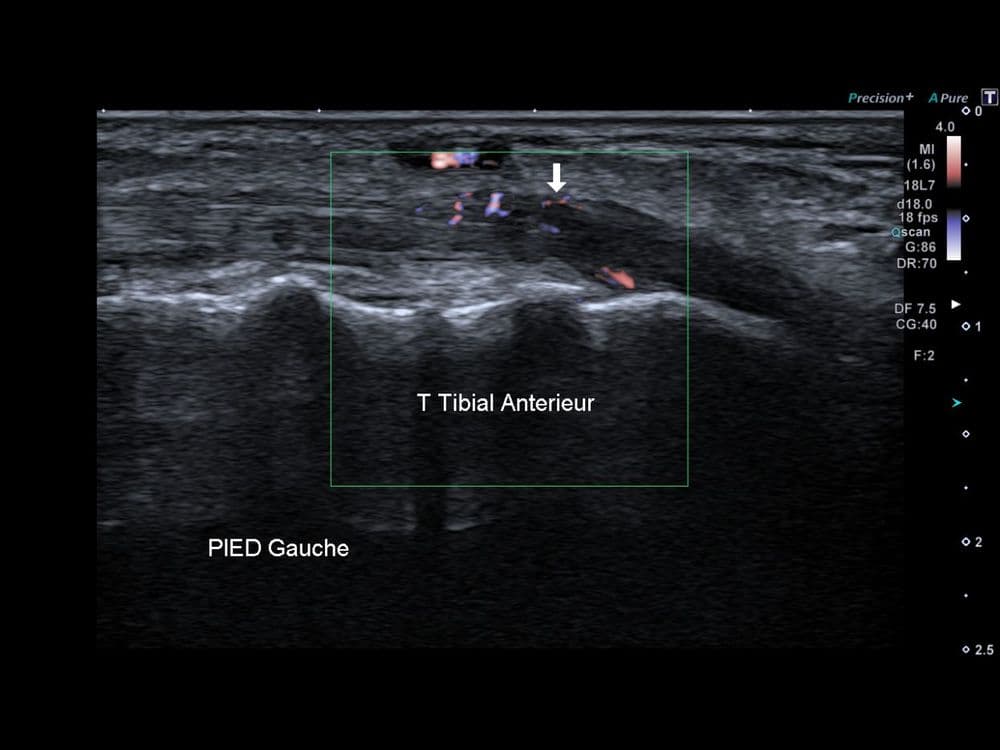

Douleur non traumatique du bord médial du pied gauche

US